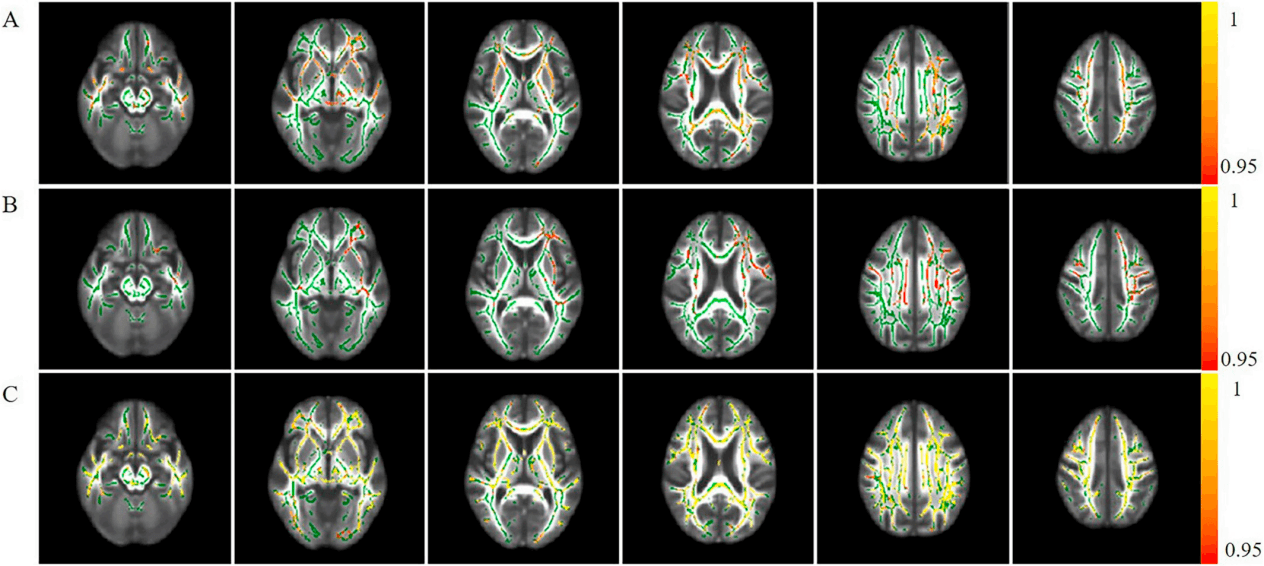

DTI数据分析系统

核心算法包括标准化的DTI数据预处理、基于体素的全脑分析(VBA)、基于白质骨架的跨被试统计分析(TBSS),以及确定性与概率性纤维追踪技术,用于构建个体化结构连接网络。